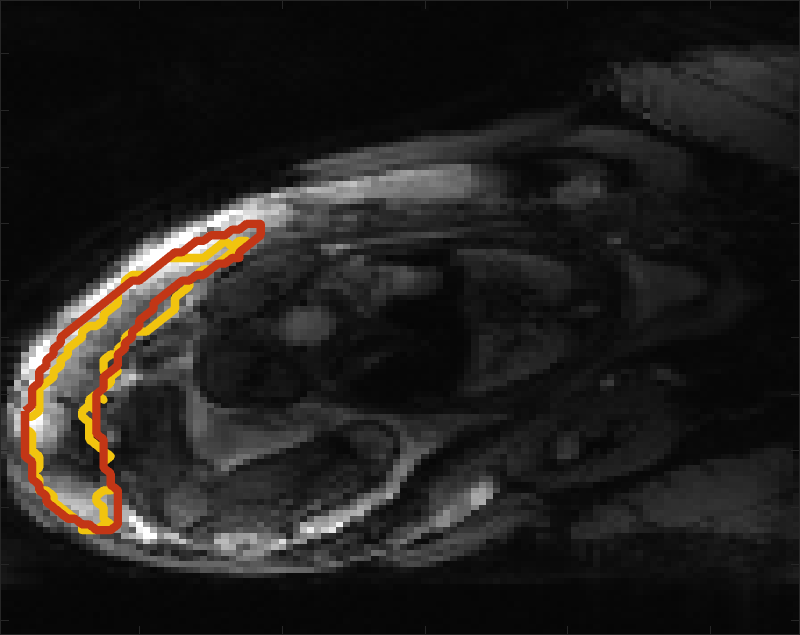

Despite its importance for many downstream clinical research tasks, placental segmentation is often performed manually and can take a significant amount of time, even for a trained expert. For BOLD MRI studies, manual segmentation is rendered more challenging due to the sheer number of MRI scans acquired and rapid signal changes due to the experimental design. Experiments acquire several hundred whole-uterus MRI scans to observe signal changes in three stages: i) normoxic (baseline), ii) hyperoxic, and iii) return to normoxic. During the hyperoxic stage, the BOLD signals increase rapidly, leading to hyperintensity throughout the placenta. Furthermore, the placental shape can undergo large deformation caused by maternal breathing, contractions, and fetal motion which can be particularly increased during hyperoxia [25]. See Fig. 1 for two examples.

Fig 3 compares the predicted label maps with ground truth on subjects with increasing Dice scores using the BW-CE model. The model accurately identifies the location of the placenta, but in the worst cases misses boundary details.